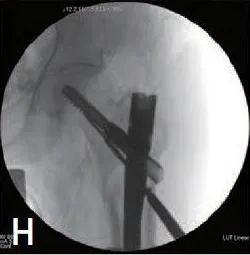

通过插入的克氏针引入部分螺纹空心螺钉。使用 6.5mm部分螺纹空心螺钉或 5.0mm部分螺纹空心螺钉来匹配克氏针的尺寸(如果使用 2.8mm克氏针,则选择 6.5mm部分螺纹空心螺钉。如果最初那样插入 2.0mm克氏针,使用 5.0 mm空心螺钉(图1 H))。最初认为高度不稳定且近端碎片位于髓内的病例,用6.5mm空心螺钉更有助于实现更安全的髓外复位。相反,最初具有相对较好的骨质量并显示出中间或髓外移位骨折模式的患者更适合5.0mm空心螺钉,以尽量减少骨折部位骨与骨接触的干扰。

图1H 通过克氏针插入5.0mm部分螺纹的辅助复位螺钉。